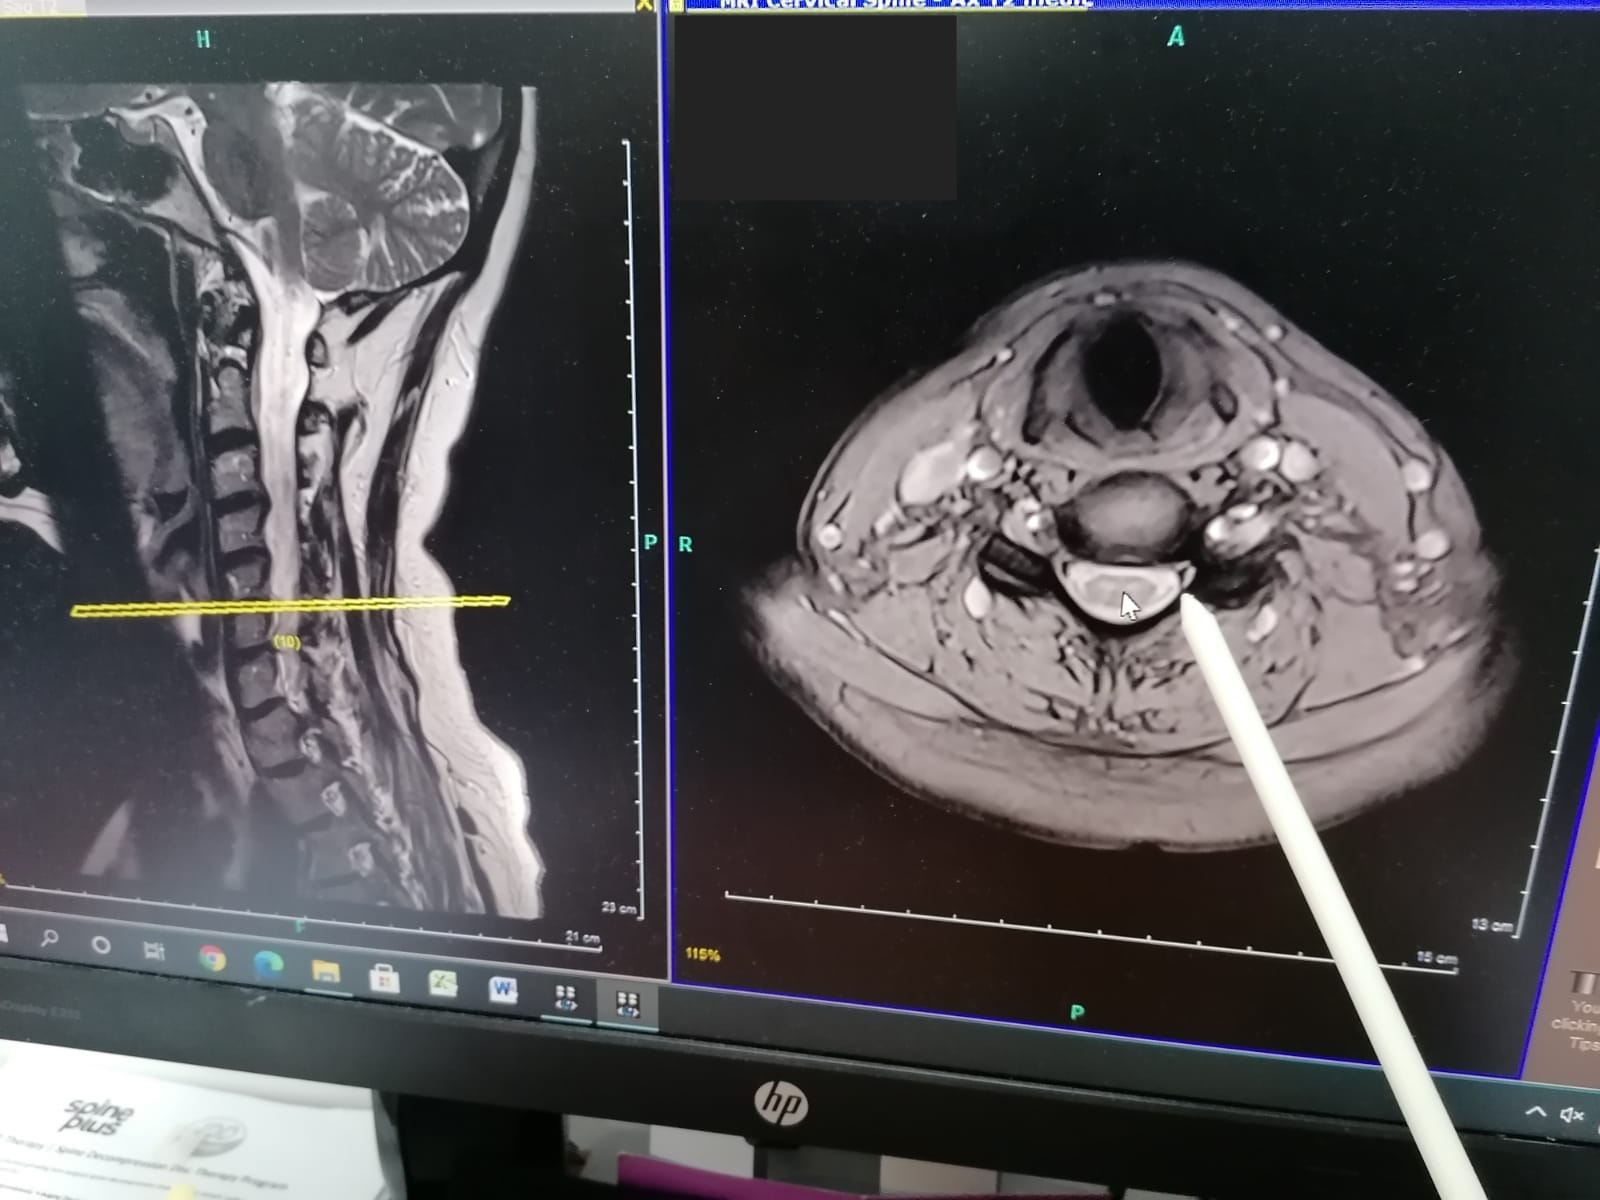

Do I need an MRI Scan to Receive IDD Therapy

Yes. To receive IDD Therapy need to have had an MRI scan (of your neck or lower back), this is so we can assess your suitablity and so we know which disc to target. Learn more about IDD Therapy - click here.

Can you refer me for an MRI scan

Yes! We work closely with several MRI centres, we have "preferred status" with these centres (such as InHealth Hornchurch) and can organise specialised spinal sequences, and MRI reports from specified radiologists from the Royal National Orthopaedic Hospital (UK's leading radiologists), at no extra cost. Such sequences and reports are usually obtainable elsewhere (including on the NHS). The average cost of spinal MRI' scans we organise is £350. Furthermore, our Osteopaths have received specialist training in spinal MRI interpretation and making MRI referrals.